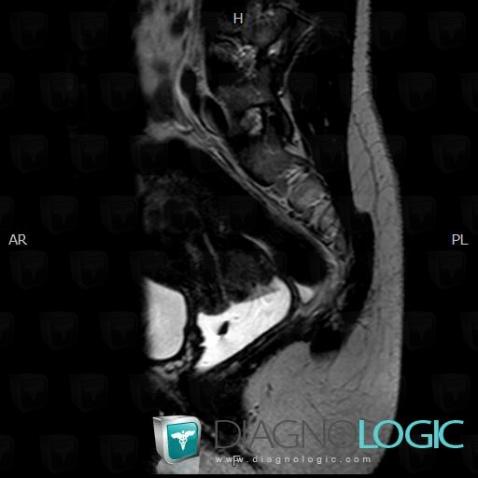

Cervical carcinoma, Uterus, MRI

Here is the specific information in the key image above:

- Diagnosis Cervical carcinoma, Location(s) Uterus, with gamuts Cervical mass